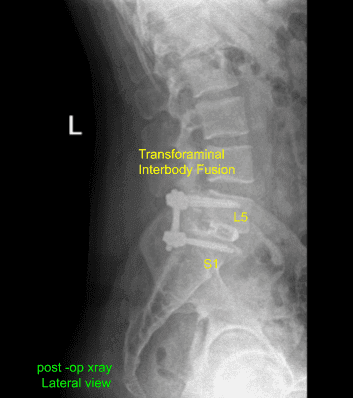

La radiografía postoperatoria mostró que hay una lordosis lumbar normal. No había anomalías ni fracturas destructivas. Los espacios del disco intervertebral parecen conservados. No hubo espondilolistesis. Las articulaciones facetarias parecen poco destacables.

El paciente hizo un seguimiento en nuestra consulta dos semanas después de la cirugía, con sus imágenes postoperatorias. Durante esta visita hablamos de programas de ejercicio en casa para la rehabilitación de la espalda. Repasamos las radiografías y el procedimiento quirúrgico. Acordaron continuar con el hielo para minimizar la inflamación y seguir utilizando movilización temprana y profilaxis mecánica para reducir las probabilidades de una trombosis venosa profunda.